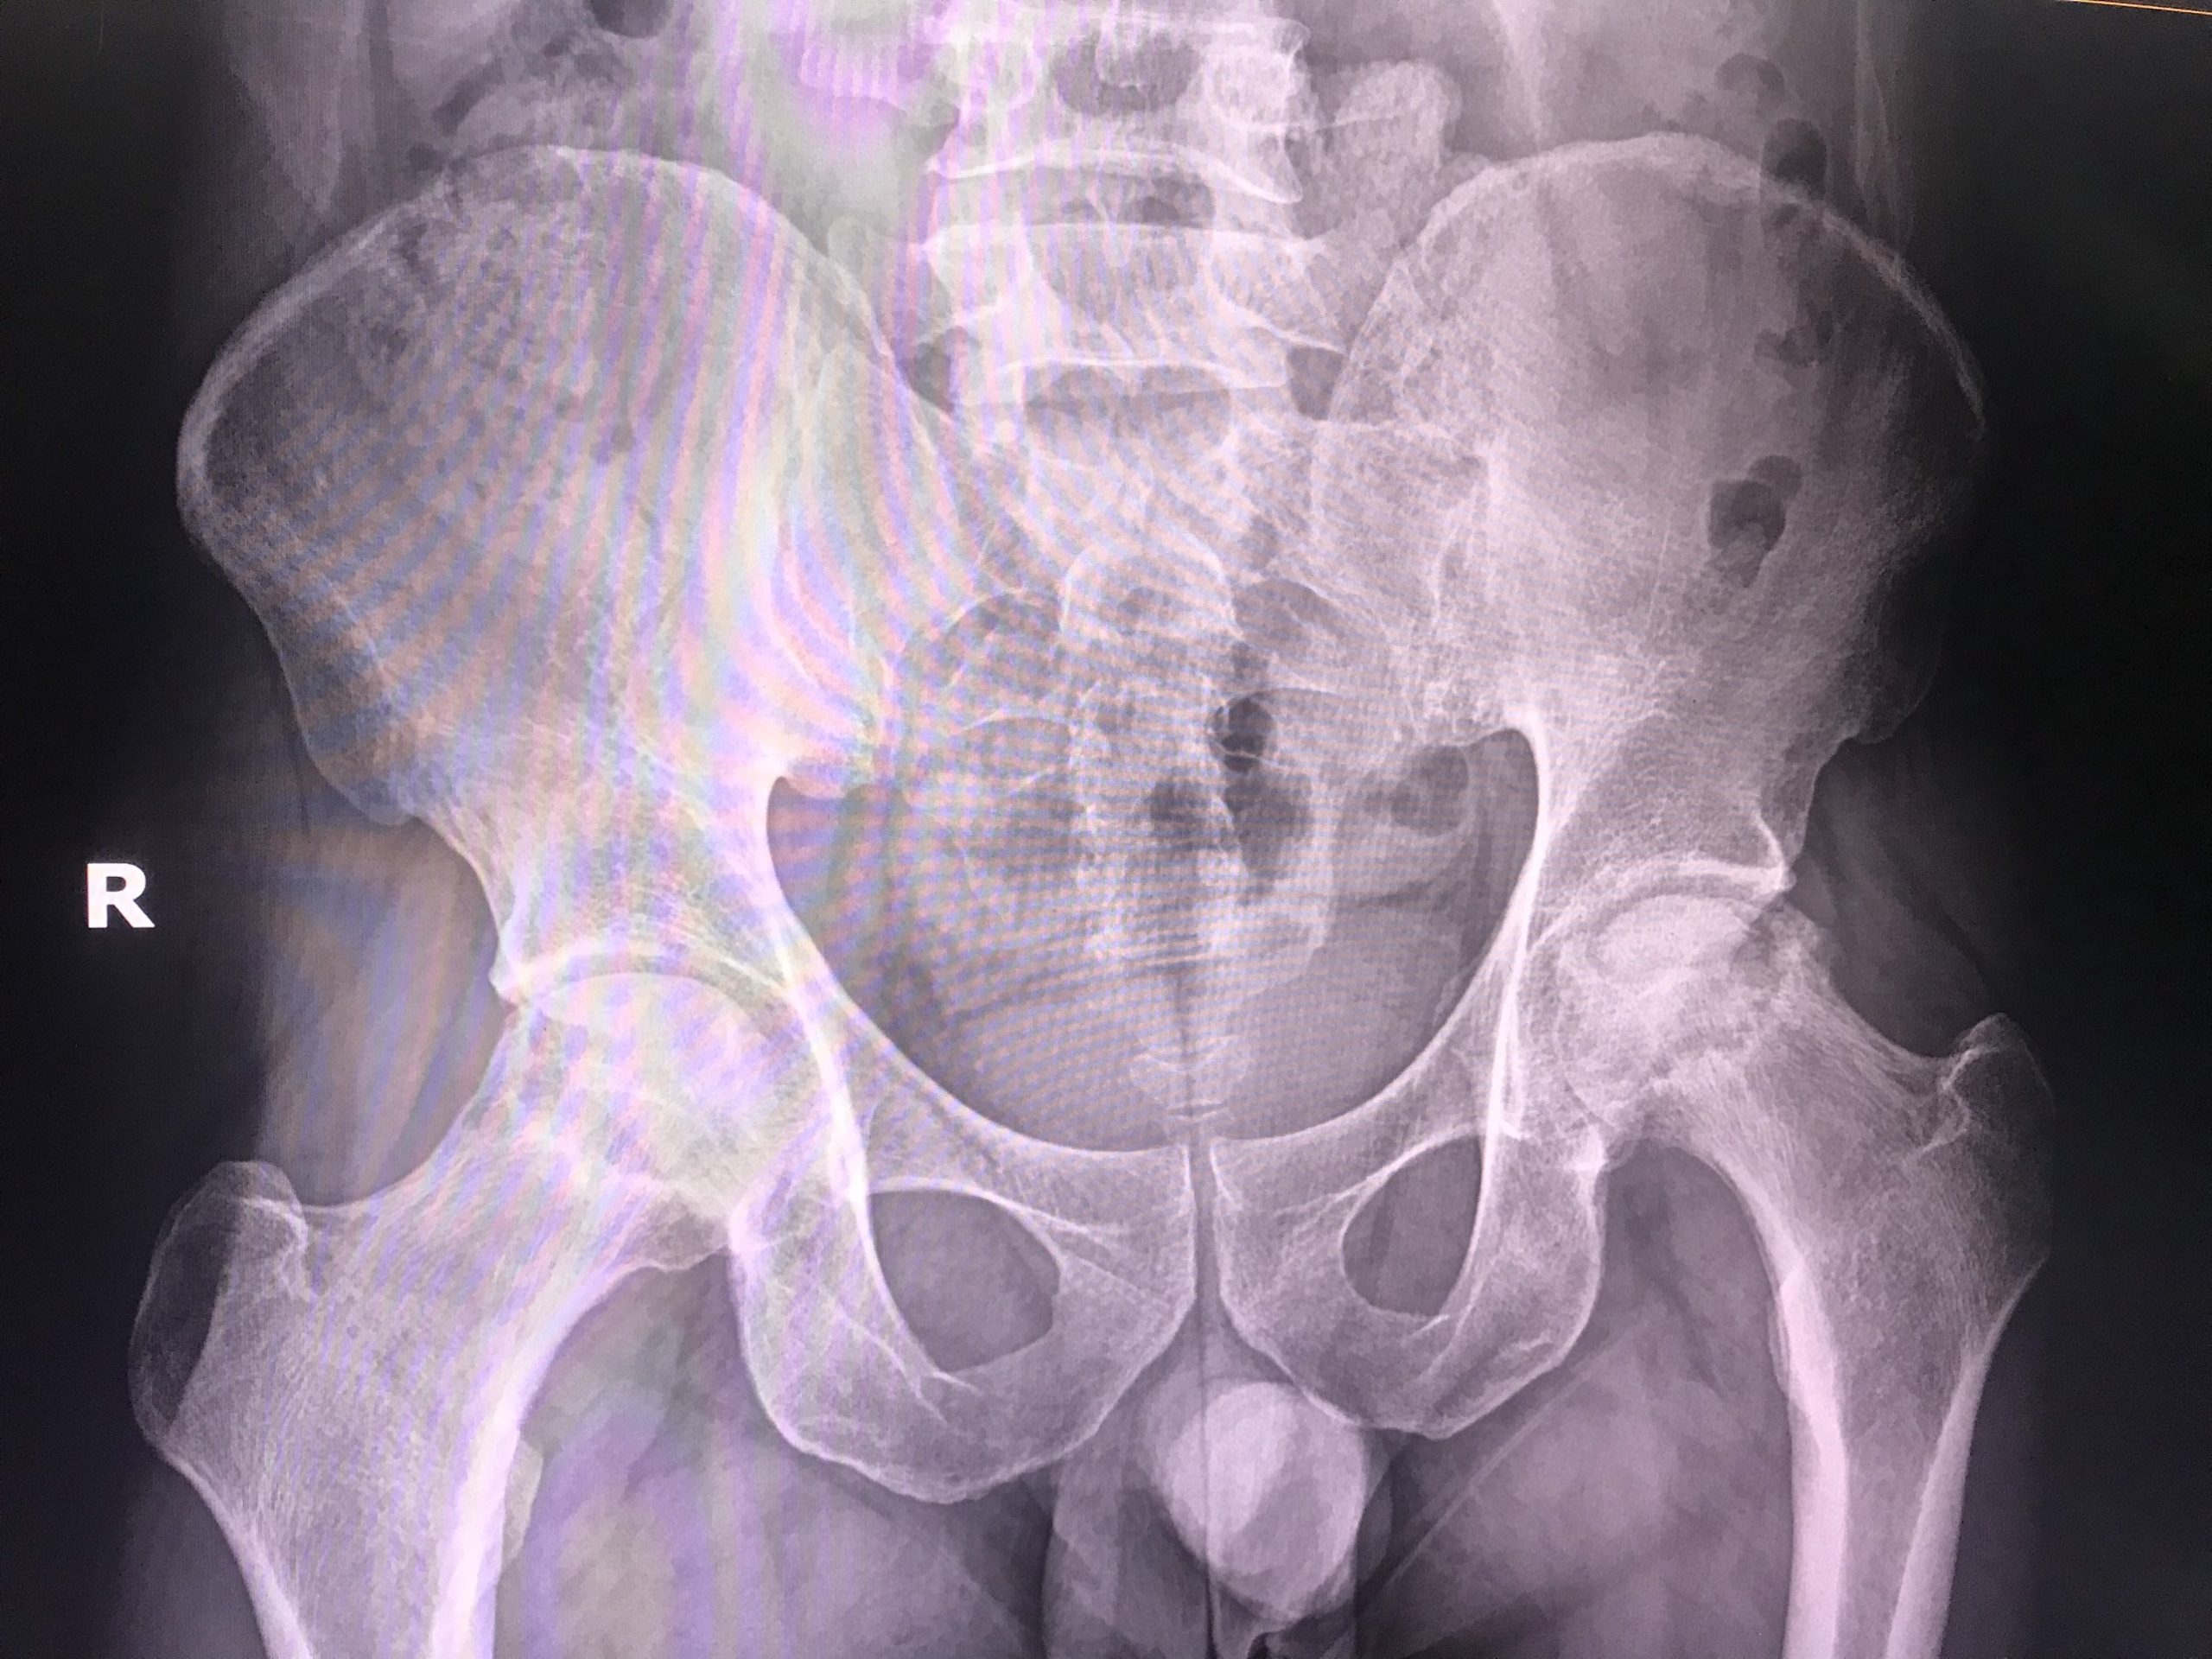

Qua hình ảnh chụp Xquang cho thấy hình ảnh đặc xương, tiêu xương và xẹp chỏm xương đùi trái. Hình ảnh chụp CT Scanner cho kết quả hình ảnh tiêu chỏm xương đùi độ III.

Nhằm giúp người bệnh chấm dứt cơn đau, trở lại vận động, lao động và sinh hoạt bình thường, sau khi hội chẩn, các bác sĩ TTYT huyện Yên Lập cùng với các chuyên gia đưa ra phương pháp phẫu thuật thay khớp háng trái toàn phần. Sau khi nghe giải thích về tình trạng bệnh và tư vấn về phương pháp điều trị, anh H. và gia đình thống nhất đồng ý phẫu thuật với nguyện vọng mở ra cho người bệnh cơ hội thoát khỏi cơn đau xương khớp dai dẳng, hồi sinh vận động.